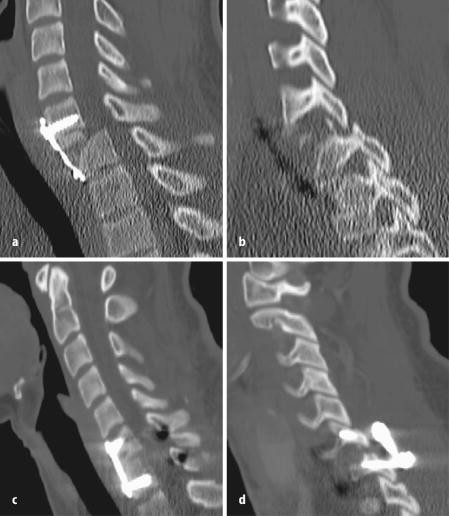

- Computertomographie (CT): Eine CT-Untersuchung kann verwendet werden, um detaillierte Bilder der Knochenstrukturen zu liefern und Wirbelbrüche oder andere strukturelle Anomalien aufzudecken.

Chirurgische Eingriffe zur Dekompression der Wirbelsäule

In einigen Fällen kann eine chirurgische Behandlung erforderlich sein, um die Kompression der Rückenwirbel zu lösen. Diese Eingriffe zielen darauf ab, den Druck auf die Nerven in der Wirbelsäule zu verringern und die Symptome zu lindern. Es gibt verschiedene Arten von chirurgischen Eingriffen, die je nach Schwere der Kompression empfohlen werden können.

- Laminektomie: Bei diesem Verfahren wird ein Teil des Wirbelbogens entfernt, um Platz für die Nervenwurzeln zu schaffen. Dies kann den Druck auf die Nerven lindern und die Symptome verbessern.

- Bandscheibenoperation: Wenn die Kompression durch eine Bandscheibenvorwölbung oder einen Bandscheibenvorfall verursacht wird, kann eine Operation erforderlich sein, um die betroffene Bandscheibe zu entfernen oder zu reparieren. Dadurch wird der Druck auf die umliegenden Nerven reduziert.

- Wirbelsäulenfusion: In einigen Fällen kann eine Operation zur Fusion der betroffenen Wirbel erforderlich sein, um die Stabilität der Wirbelsäule wiederherzustellen und den Druck auf die Nerven zu verringern.